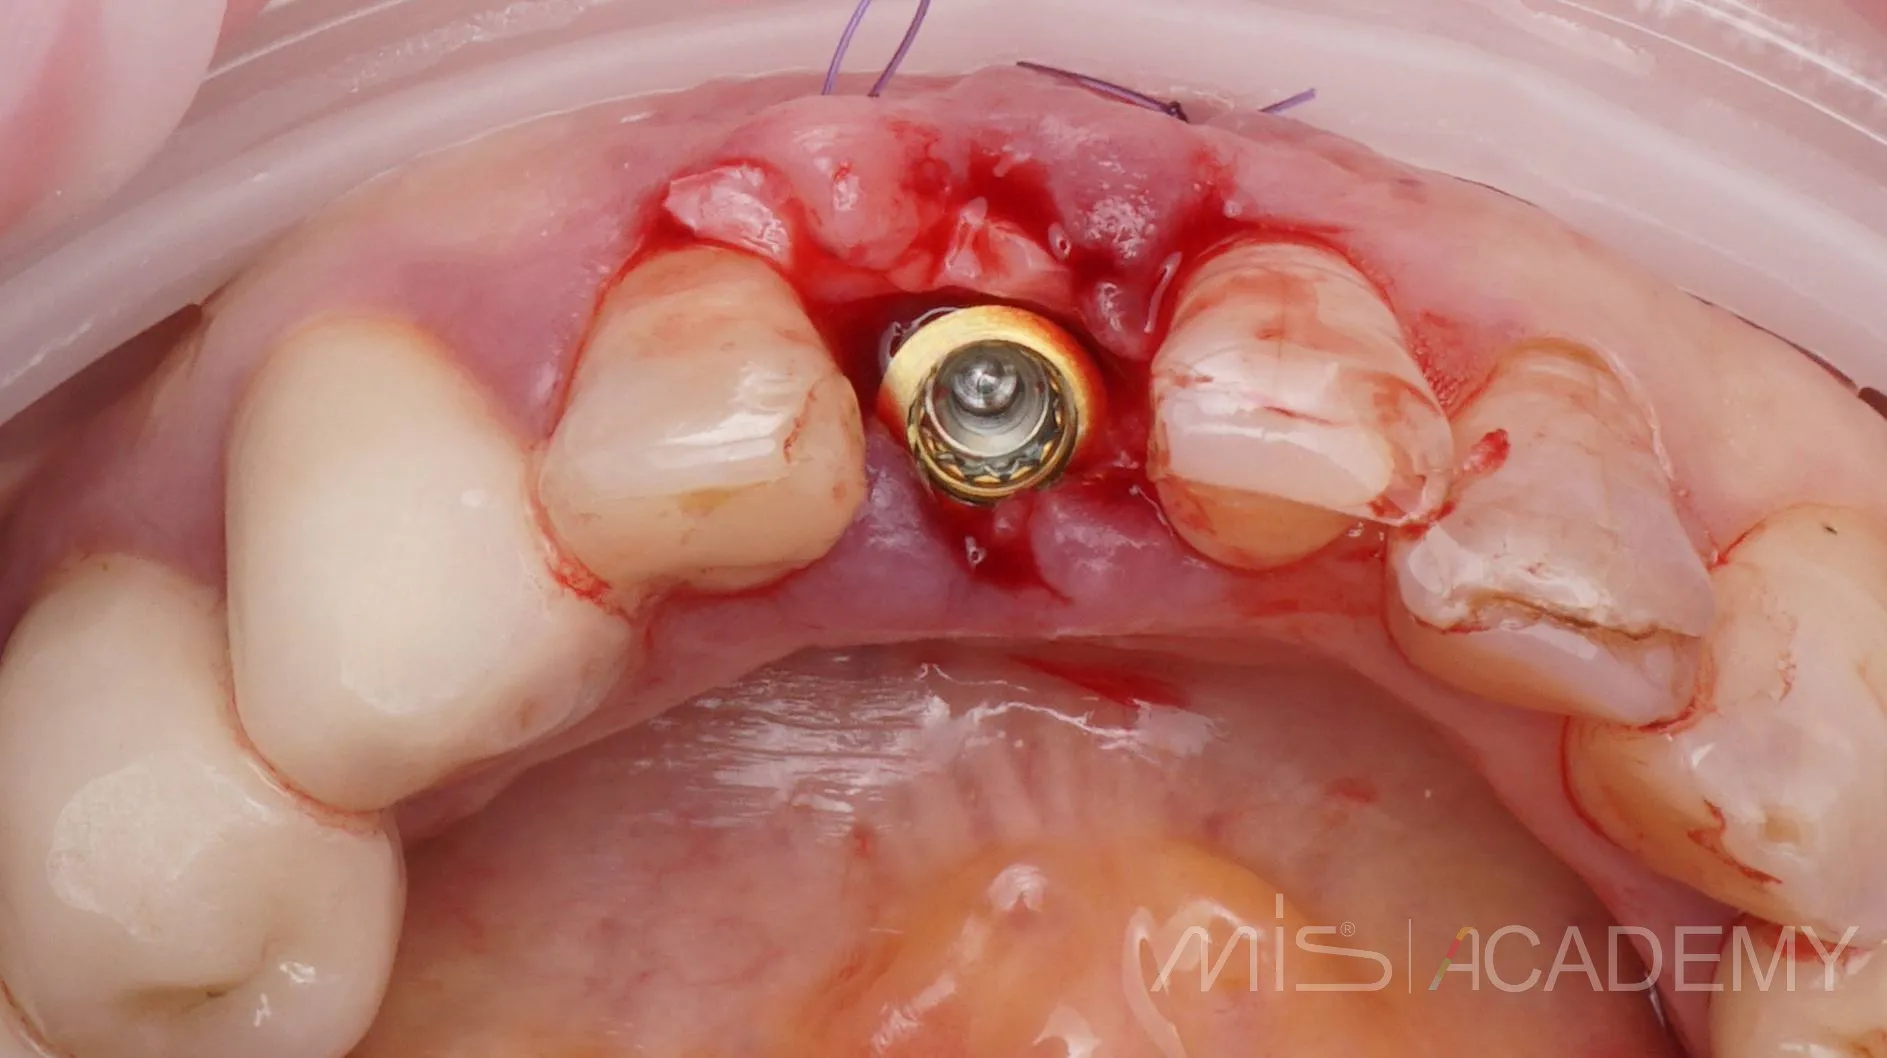

Одномоментная имплантация MIS С1

— Индивидуальный Zr формирователь десны на Connect абатменте